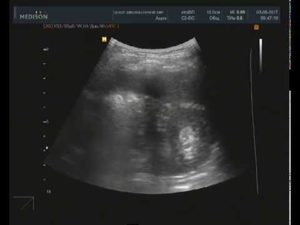

- УЗИ обеих почек – позволяет оценить размеры, структуру, однородность тканей органа, а также выявить имеющиеся уплотнения и определить их размер.

Основу диагностики опухоли почки составляют инструментальные методы обследования. Самым простым и доступным является УЗ-сканирование забрюшинного пространства. Во время УЗИ можно выявить объемное образование почек, оценить такие параметры, как:

- размер и структуру опухоли,

- деформацию контура почечной капсулы,

- наличие очагов кровооизлияния и некроза,

- состояние кровотока в образовании и самом органе,

- сопутствующие изменения со стороны мочевыводящих путей.

Ангиомиолипома может быть диагностирована случайно при прохождении УЗИ. На экране на фоне нормальной паренхимы четко просматривается уплотнение.

Данная методика позволяет оценить диаметр, эхогенность и структуру нароста.

- УЗИ. Помогает выявить уплотнение, оценить его диаметр и структуру;

Ангиолипомное образование почек при размерах до 400 мм протекает безболезненно. Объясняется это тем, что почечная паренхима не имеет болевых рецепторов. Диагностируется, как правило, заболевание случайным образом во время ультразвукового исследования пациента или на КТ.